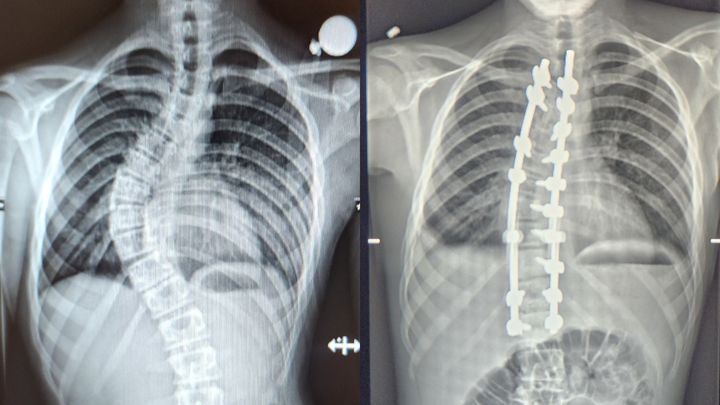

Kayden went into surgery today to have a Spinal Fusion to correct a 60 degree curve that appeared within the past year. Due to the rapid development, he was given a time-line of several months before the curve got significantly worse, and the decision was made to go forward with the surgery to avoid further damage and a difficult life leading to complications such as degenerative disc disease and and potentially being wheelchair bound.